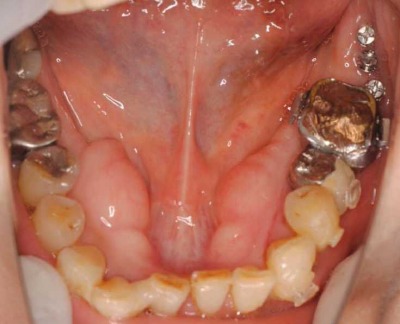

左下前歯の重なりが無くなって、きれいになったので、右も新しく装置を入れてほぼきれいに一列になってきました。

まだ、途中ですが患者様も満足されています。